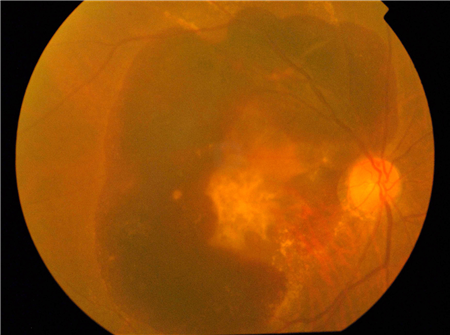

顧名思義,眼底出血發(fā)生在眼睛深處、底部的地方,即視網(wǎng)膜或玻璃體內(nèi)出血。眼底出血,光用肉眼是無法看見的,所以即使是照鏡子也不會(huì)看出有何異樣。一說到出血,很多人第一反應(yīng)就是痛,那么眼底出血眼睛會(huì)痛嗎?在早期的時(shí)候,往往不痛不癢,需用專門的醫(yī)學(xué)檢查儀器才能發(fā)現(xiàn)。

眼底出血雖然“深藏不露”,但危險(xiǎn)性卻比眼表出血高,因?yàn)榘l(fā)生眼底出血若不及時(shí)治療,不僅影響視力,嚴(yán)重情況下還可能導(dǎo)致眼睛失明,這也是眼底出血的可怕之處。

不過,隨著病情的發(fā)展,眼底出血也會(huì)表現(xiàn)出一些癥狀:視物變形、眼前有黑影飄動(dòng)、視野缺損、視野中央有黑點(diǎn)等,如果出現(xiàn)了這些異常癥狀,可要多“長(zhǎng)個(gè)心眼”,應(yīng)及時(shí)前往眼科醫(yī)院檢查。